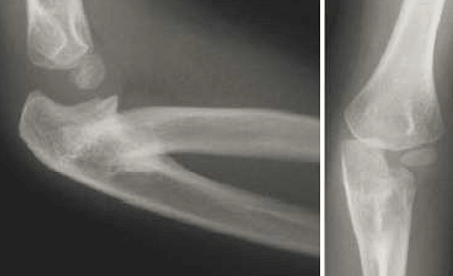

Radiographic evaluation revealed radioulnar synostosis, an isolated congenital autosomal dominant condition characterized by the osseous union of the proximal ends of the radius and ulna. During embryonic development, the two bones fail to separate. ... Content Retrieval

Radiographic evaluation revealed radioulnar synostosis, an isolated congenital autosomal dominant condition characterized by the osseous union of the proximal ends of the radius and ulna. During embryonic development, the two bones fail to separate. ... Retrieve Content

V. Karatosun et al.: Congenital radioulnar synostosis 315 Fig. 1.Anteroposterior plain radiographs of both elbows. In the right elbow, osseous fusion typical of complete proximal ... View This Document

Vol. 8, No.6 November 1983 Congenital radioulnar synostosis 833 Fig. 4. Radiologically, a broad spectrum of synostosis is seen. A, Virtually total synostosis; B, ... Access Full Source

Fig. 8.4 Radiohumeral synostosis, ulnohumeral synostosis This a 5-year-old boy has a more common presentation of bilateral synostosis. On his left side the radius is fused and the ulna is still separated from the ... Get Content Here